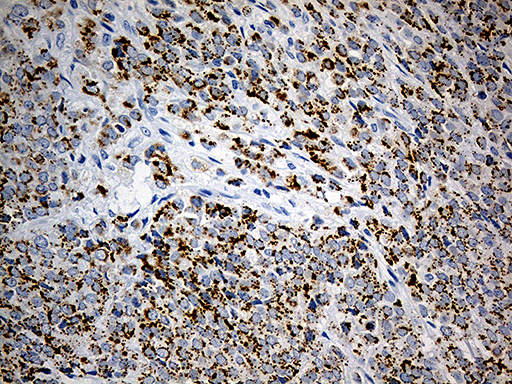

Immunohistochemical staining of paraffin-embedded human stomach carcinoma using anti-MUC1 (EMA) mouse monoclonal antibody at 1:200 dilution of1mg/mL using Polink2 Broad HRP DAB for detection. BD-PE0664 requires heat-induced epitope retrieval with Accel pH8.7 at 110°C for 3min using pressure chamber/cooker. The image is a composite of 3 tumors which show strong membranous and cytoplasmic staining in >75 % tumor cells.